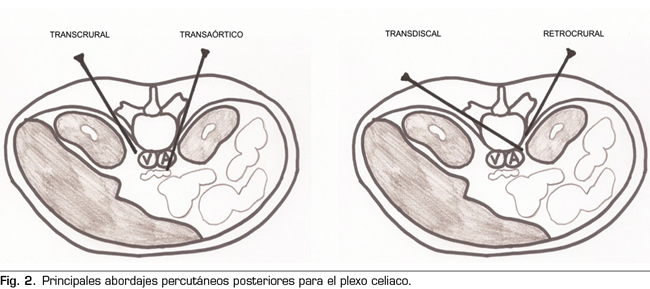

Aclarada esta cuestión, podemos clasificar los abordajes percutáneos de la siguiente manera (Figura 2):

– Abordaje transcrural: el más utilizado para el bloqueo del plexo celiaco (Figura 3). El paciente se coloca en decúbito prono, identificando el cuerpo vertebral L1 y avanzando una aguja por cada lado, a unos 7,5 cm de la línea media, hasta atravesar la crura diafragmática y bloquear el plexo.

– Abordaje retrocrural: abordaje que clásicamente se ha descrito tanto para el bloqueo del plexo celiaco (a nivel L1) como para los nervios esplácnicos. En el abordaje retrocrural puro, el paciente se coloca en decúbito prono y se localizan los cuerpos vertebrales de T11 y T12, avanzando las agujas hasta el tercio anterior de estos y bloqueando así los nervios esplácnicos.

– Abordaje transaórtico: descrito por Ischia y cols. (14), se trata de un abordaje unilateral con el paciente en decúbito prono, accediendo desde el lado izquierdo del cuerpo vertebral de L1 hasta atravesar la aorta y quedando la punta de la aguja anterior a esta. Se apreciará salida de sangre en el momento en el que atravesemos la arteria, con un cese posterior en cuanto nos dispongamos anteriores a ella. Se ha visto que el riesgo de hemorragia oculta es bajo, ya que en esta zona la aorta se encuentra reforzada por las cruras diafragmáticas y la fascia prevertebral. Sin embargo, las publicaciones son escasas y son necesarios estudios de mayor evidencia científica. Las contraindicaciones específicas para este abordaje son la presencia de aneurisma de aorta abdominal, trombo mural y calcificaciones.

– Abordaje transdiscal: se realiza bajo control TAC atravesando el disco intervertebral T12-L1 hasta alcanzar los nervios esplácnicos. Aunque la bibliografía es escasa, con este abordaje se consigue teóricamente disminuir el riesgo de complicaciones como paraplejia, neumotórax y perforación hepática o renal, ya que la aguja se introduce más cerca de la línea media, siendo de gran utilidad en pacientes con alteraciones anatómicas alrededor del plexo celiaco o en pacientes con organomegalias (15,16).

– Abordaje abdominal: utilizado normalmente bajo visión ecográfica por vía anterior.